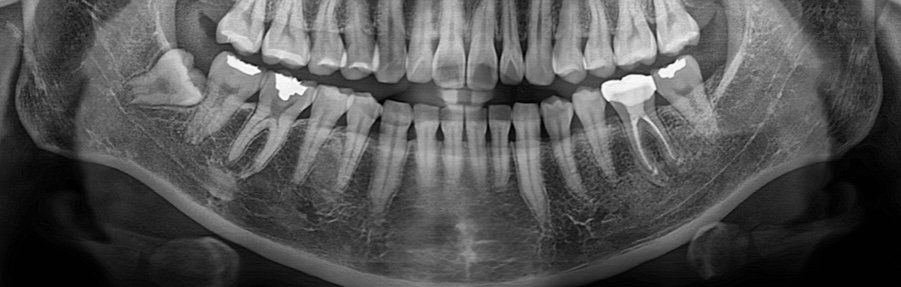

하악 사랑니 발치 난이도가 어떤가요?

아직 증상은 없지만,하악 사랑니를 빼야할 것 같아서 병원 예약했는데요 너무 무섭고, 걱정돼서 질문드려요!

엑스레이는 두달 전 사진입니다

1. 하악 사랑니 발치 난이도가 종합적으로 어떤가요?

2.옆 어금니랑 사랑니가 겹쳐있어 보이는데..사랑니가 어금니를 흡수한 건 까진 아니겠죠?ㅠㅠㅠㅠ

3. 발치시, 뼈 삭제를 많이 해야하는 매복도인가요?

48번 발치계획중인것으로 보입니다. 뿌리과 신경관이 겹쳐있는것으로 보입니다. 이 부분은 씨티촬영을 통해서 확인해보는게 좋을 것입니다.

뿌리가 보여있는 형태라서 발치가 아주 어려운 편은 아닐 것으로 보입니다. 하지만 치아를 분리하고 뒤쪽 골을 일부 삭제해야합니다.

앞의 치아를 흡수하고 있는것으로 보이진 않습니다.

1. 단순 매복과는 다르며 치아를 부분적으로 절단하여 뽑아야할 가능성이 있습니다. 또한 뿌리 부분이 신경과 맞닿아 있을 가능성도 있으므로 dental CT 등으로 확인해볼 필요가 있습니다.

2. 일부 흡수에 영향을 주고 있는 상황입니다. 따라서 빠른 발치가 필요해보입니다.

2. 뼈 삭제를 해야할 가능성이 높아 보입니다.

수평매복 사랑니 입니다. 사랑니 뽑는 수술할 때 사랑니를 부수고 덮고 있는 뼈도 삭제해야 합니다. 또한 사랑니 뿌리끝과 신경관이 맞닿아 있어 드물게 감각이상이 올 수도 있지만 발치해야 합니다. 그냥두면 바로 앞 어금니 뒤쪽이 상하게 됩니다.

해당되는 사랑니는 완전매복으로 발치시에 치조골삭제와 치아 삭제를 상대적으로 많이 해야 하는 케이스 입니다.

현재 사랑니가 치아를 흡수하지 않고 있고 잇몸밖으로 나오지도 않았기 때문에 염증이나 주변치아에 문제를 발생시킬 위험이 없어 발치를 하지 않아도 괜찮아요.